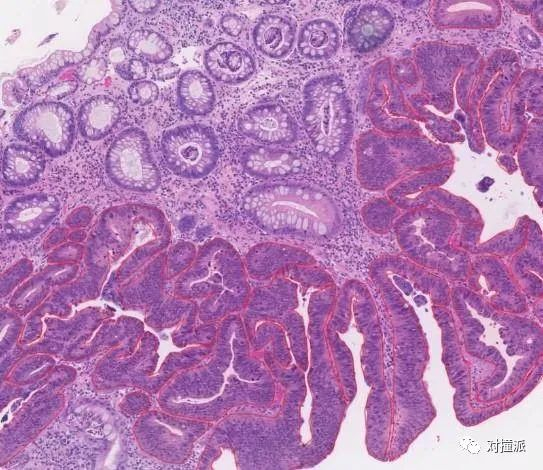

病理检查,建立在活检之上,通过分析切片来提供诊断建议。进行病理影像判读,需要用肉眼观察细胞甚至分子层面的微观特征,对医生的经验要求非常高。

相比于影像科,病理数据图像复杂,标注的所需要的人力和时间投入更大。

一位做过AI医疗研究的人回忆,“最难的就是病理的分析,可能一个病理样本上面需要关注100多个点,可能一个十几年经验的医生都需要看一两个小时,还不一定准。”

衡道公开的消化道病理数据集样本